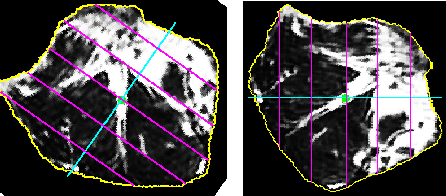

2.6 Fragmenting ES muscles

The next step is to quantify fat in fragmented regions of the erector spinae (ES) muscles. The segmented muscles could be sub-divided into many regions. We have subdivided the segmented muscles into six regions with reference to the centre of the spinal column, as shown in Figure 8 and Figure 9. The use of six fragments was based solely on visual observation by a clinical biomechanist and clearly needs further research. Generally, the segmented muscle region is irregularly shaped. The boundary points are extracted and used to sub-divide the region into smaller segments. After obtaining the various segments, the fat content percentage in each segment is calculated.

The following steps are used to subdivide the segmented region and to perform the computations:

Step 1: The centre of the spinal column is automatically detected for a given input image.

Step 2: A radial line from the centre of the spinal column , which passes through the centroid of the segmented muscle region and that bisects the ES muscles is plotted, as shown in Figure 7.

Step 3: Considering the radial line as vector and a horizontal line through the centre of the spinal column as vector , the angle between the vectors and is calculated.

Step 4: The angle is used to identify, whether the segmented muscle region lies either on the right side or the left side of the spinal column. If the angle is less than the segmented muscle region is considered to be on the right side and it is rotated by angle in the counter-clockwise direction as shown in Figure 8, else the segmented muscle region is considered to be on the left side and it is rotated by an angle in the clockwise direction as shown in Figure 9.

Step 5: From the segmented muscle region, the contour as a set of points, is extracted. Subsequently the vectors and pertaining to the contour points of the X-coordinates and Y-Coordinates, respectively, were extracted.

Step 6: The maximum and minimum values of and are found, which gives the extremities of the irregular shaped segmented muscle region.

Step 7: The length of the segmented region, which is the difference between the maxima and minima of is calculated. Further, the length is used to sub-divide the segmented muscle region.

Step 8: To have six sub-divisions, five equidistant vertical lines are plotted over the segmented lumbar muscle region at regular intervals from the minima of . These vertical lines are plotted from minima of to maxima of so that every line touches the contours of the segmented muscle region as shown in Figure 8 and Figure 9.

Step 9: Considering all seven hyperplanes, one each at the minima and maxima of and one at each of the five vertical lines, the fat content in six smaller segments are calculated.

Step 10: The fat content in every smaller segment is calculated by subjecting every pixel inside the region to the sigmoid function with the pre-selected threshold and softness level.